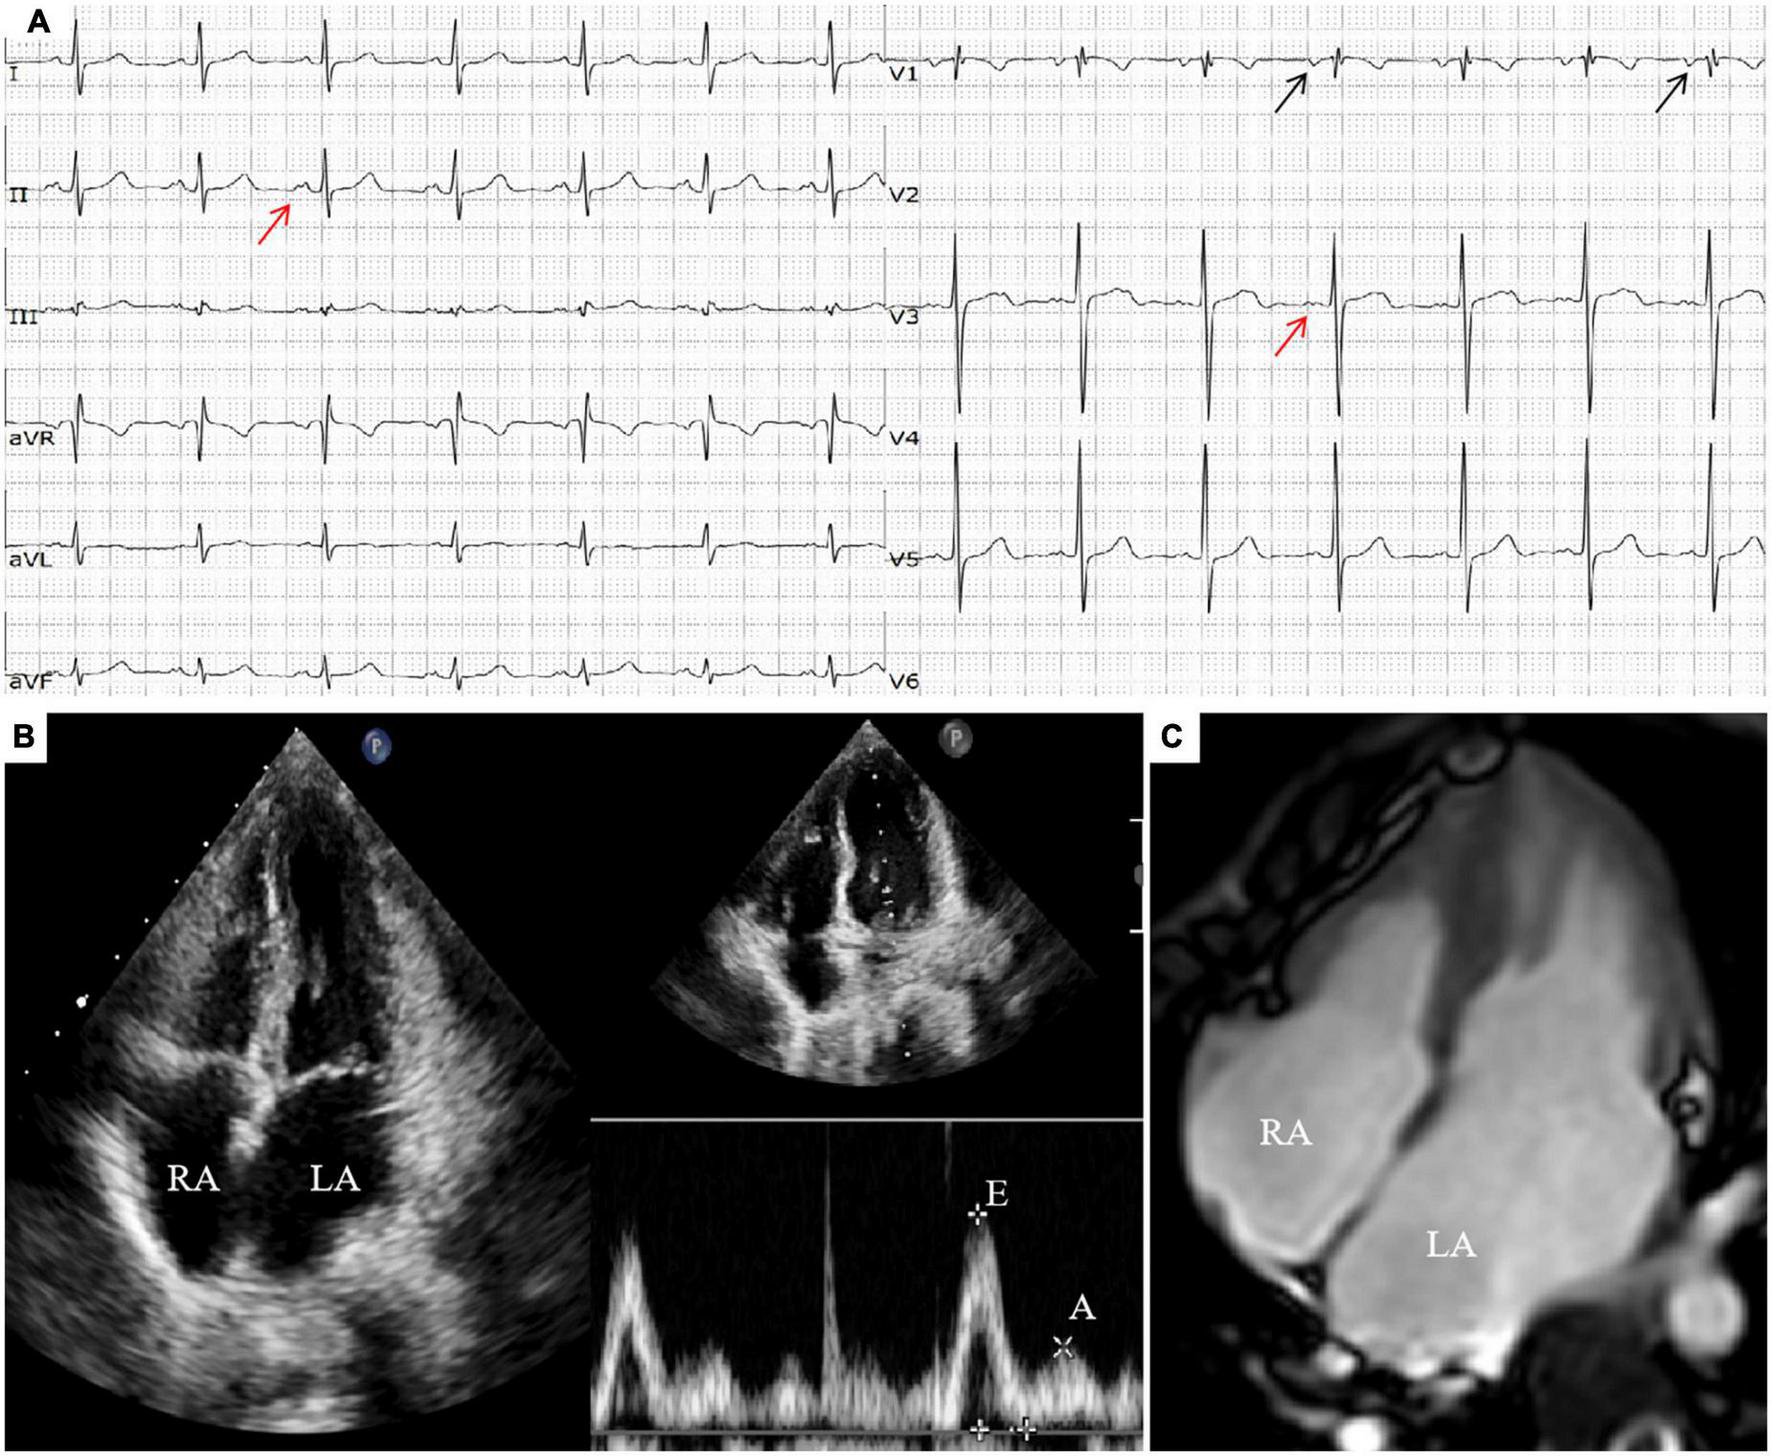

There were no obvious abnormalities in the brain MRI and video electroencephalogram (VEEG). The electrocardiogram (ECG) revealed Ptf-V1 < –0.04 mm⋅s and biphasic P waves, indicating left atrial enlargement and the chest X-ray revealed an enlarged heart shadow. The echocardiogram showed biatrial enlargement, especially in the left atrium (LA: 32 mm, RA: 30 mm), decreased diastolic function (E/A = 2.6; E Peak deceleration time 130 ms; Constant volume diastolic time 49 ms), moderate mitral valve regurgitation and left ventricular ejection fraction of 51.8%. Except for bilateral enlargement, cardiac magnetic resonance (CMR) indicated no abnormalities (see Figure 1). The ECG at the time of the AED discharge indicated ventricular fibrillation (see Figure 2). Troponin T and brain natriuretic peptide (BNP) levels were normal.

Figure 1. (A) ECG showed sinus rhythm, incomplete right bundle branch block, Ptf-V1 < –0.04 mm⋅s (the black arrow) and biphasic P waves (the red arrow). (B) Echocardiogram showed biatrial enlargement, left atrium obvious (LA: 32 mm, RA: 30 mm) and decreased diastolic function (E/A = 2.6). (C) Transverse section of CMR showed biatrial enlargement slightly.